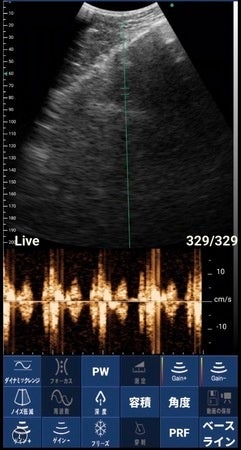

▲ポケマムサウンズで録画撮影した心音の波形

従来、産婦人科の妊婦検診でしか見られなかった胎児エコーをスマホでいつでもどこでも見られるようにした妊婦さん用の超音波エコー。記録した動画や画像は、データ送信により家族間での共有が可能。WHOの基準を満たし安心安全に使用することができる。胎児の様子が見えやすくなる妊娠12週目以降からの使用を推奨。